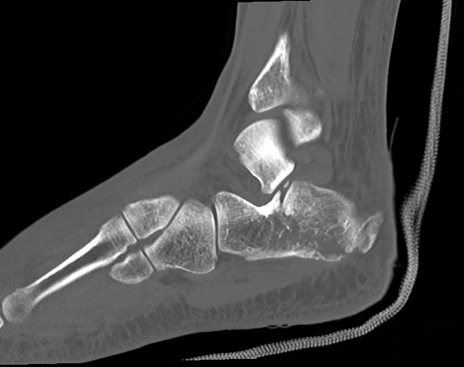

症例37 左足関節CT(矢状断像)

左足関節CT